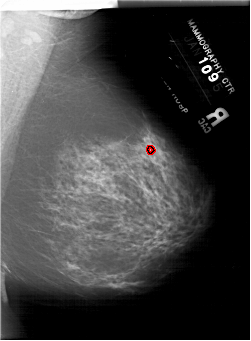

FILE: A_1919_1.RIGHT_MLO.OVERLAY

TOTAL_ABNORMALITIES 1

ABNORMALITY 1

LESION_TYPE CALCIFICATION TYPE PLEOMORPHIC DISTRIBUTION CLUSTERED

ASSESSMENT 4

SUBTLETY 2

PATHOLOGY BENIGN

TOTAL_OUTLINES 1

BOUNDARY